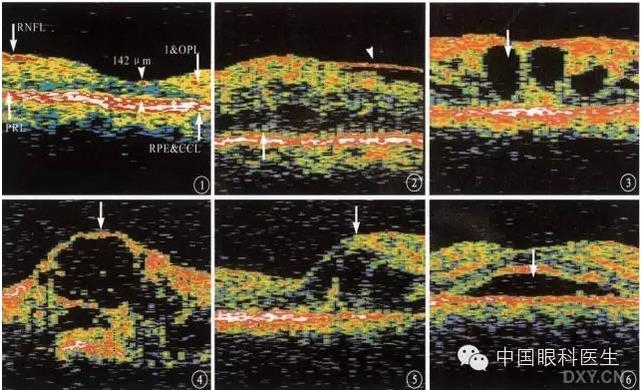

2、眼底异常结构的OCT影像:视网膜厚度改变 (如 变薄、 变厚);光反射改变(如反射增强、反射减弱、无反射)。

3、中浆:神经上皮脱离( 神经上皮与色素上皮间是无反射的暗区);色素上皮脱离(色素上皮光反射带隆起,其下方是无光反射的暗区;必须存一端和色素上皮反射带相连;均可测量出神经上皮脱离和色素上皮脱离区范围、高度)

神经上皮脱离

神经上皮、色素上皮脱离

4、视网膜前膜:前膜和视网膜的关系(距离和粘连);前膜的厚度;黄斑假性裂洞

视网膜前膜

5、黄斑水肿:海绵状无反射区;囊样无反射区;视网膜神经上皮脱离。

神经上皮脱离及囊样无反射区

6、板层黄斑裂洞:在裂洞底部仍可见到部分神经上皮及色素上皮的反射。

板层裂洞伴神经上皮脱离

7、全层裂洞:神经上皮层全层无反射,只见洞底色素上皮层反射。

裂洞伴神经上皮脱离